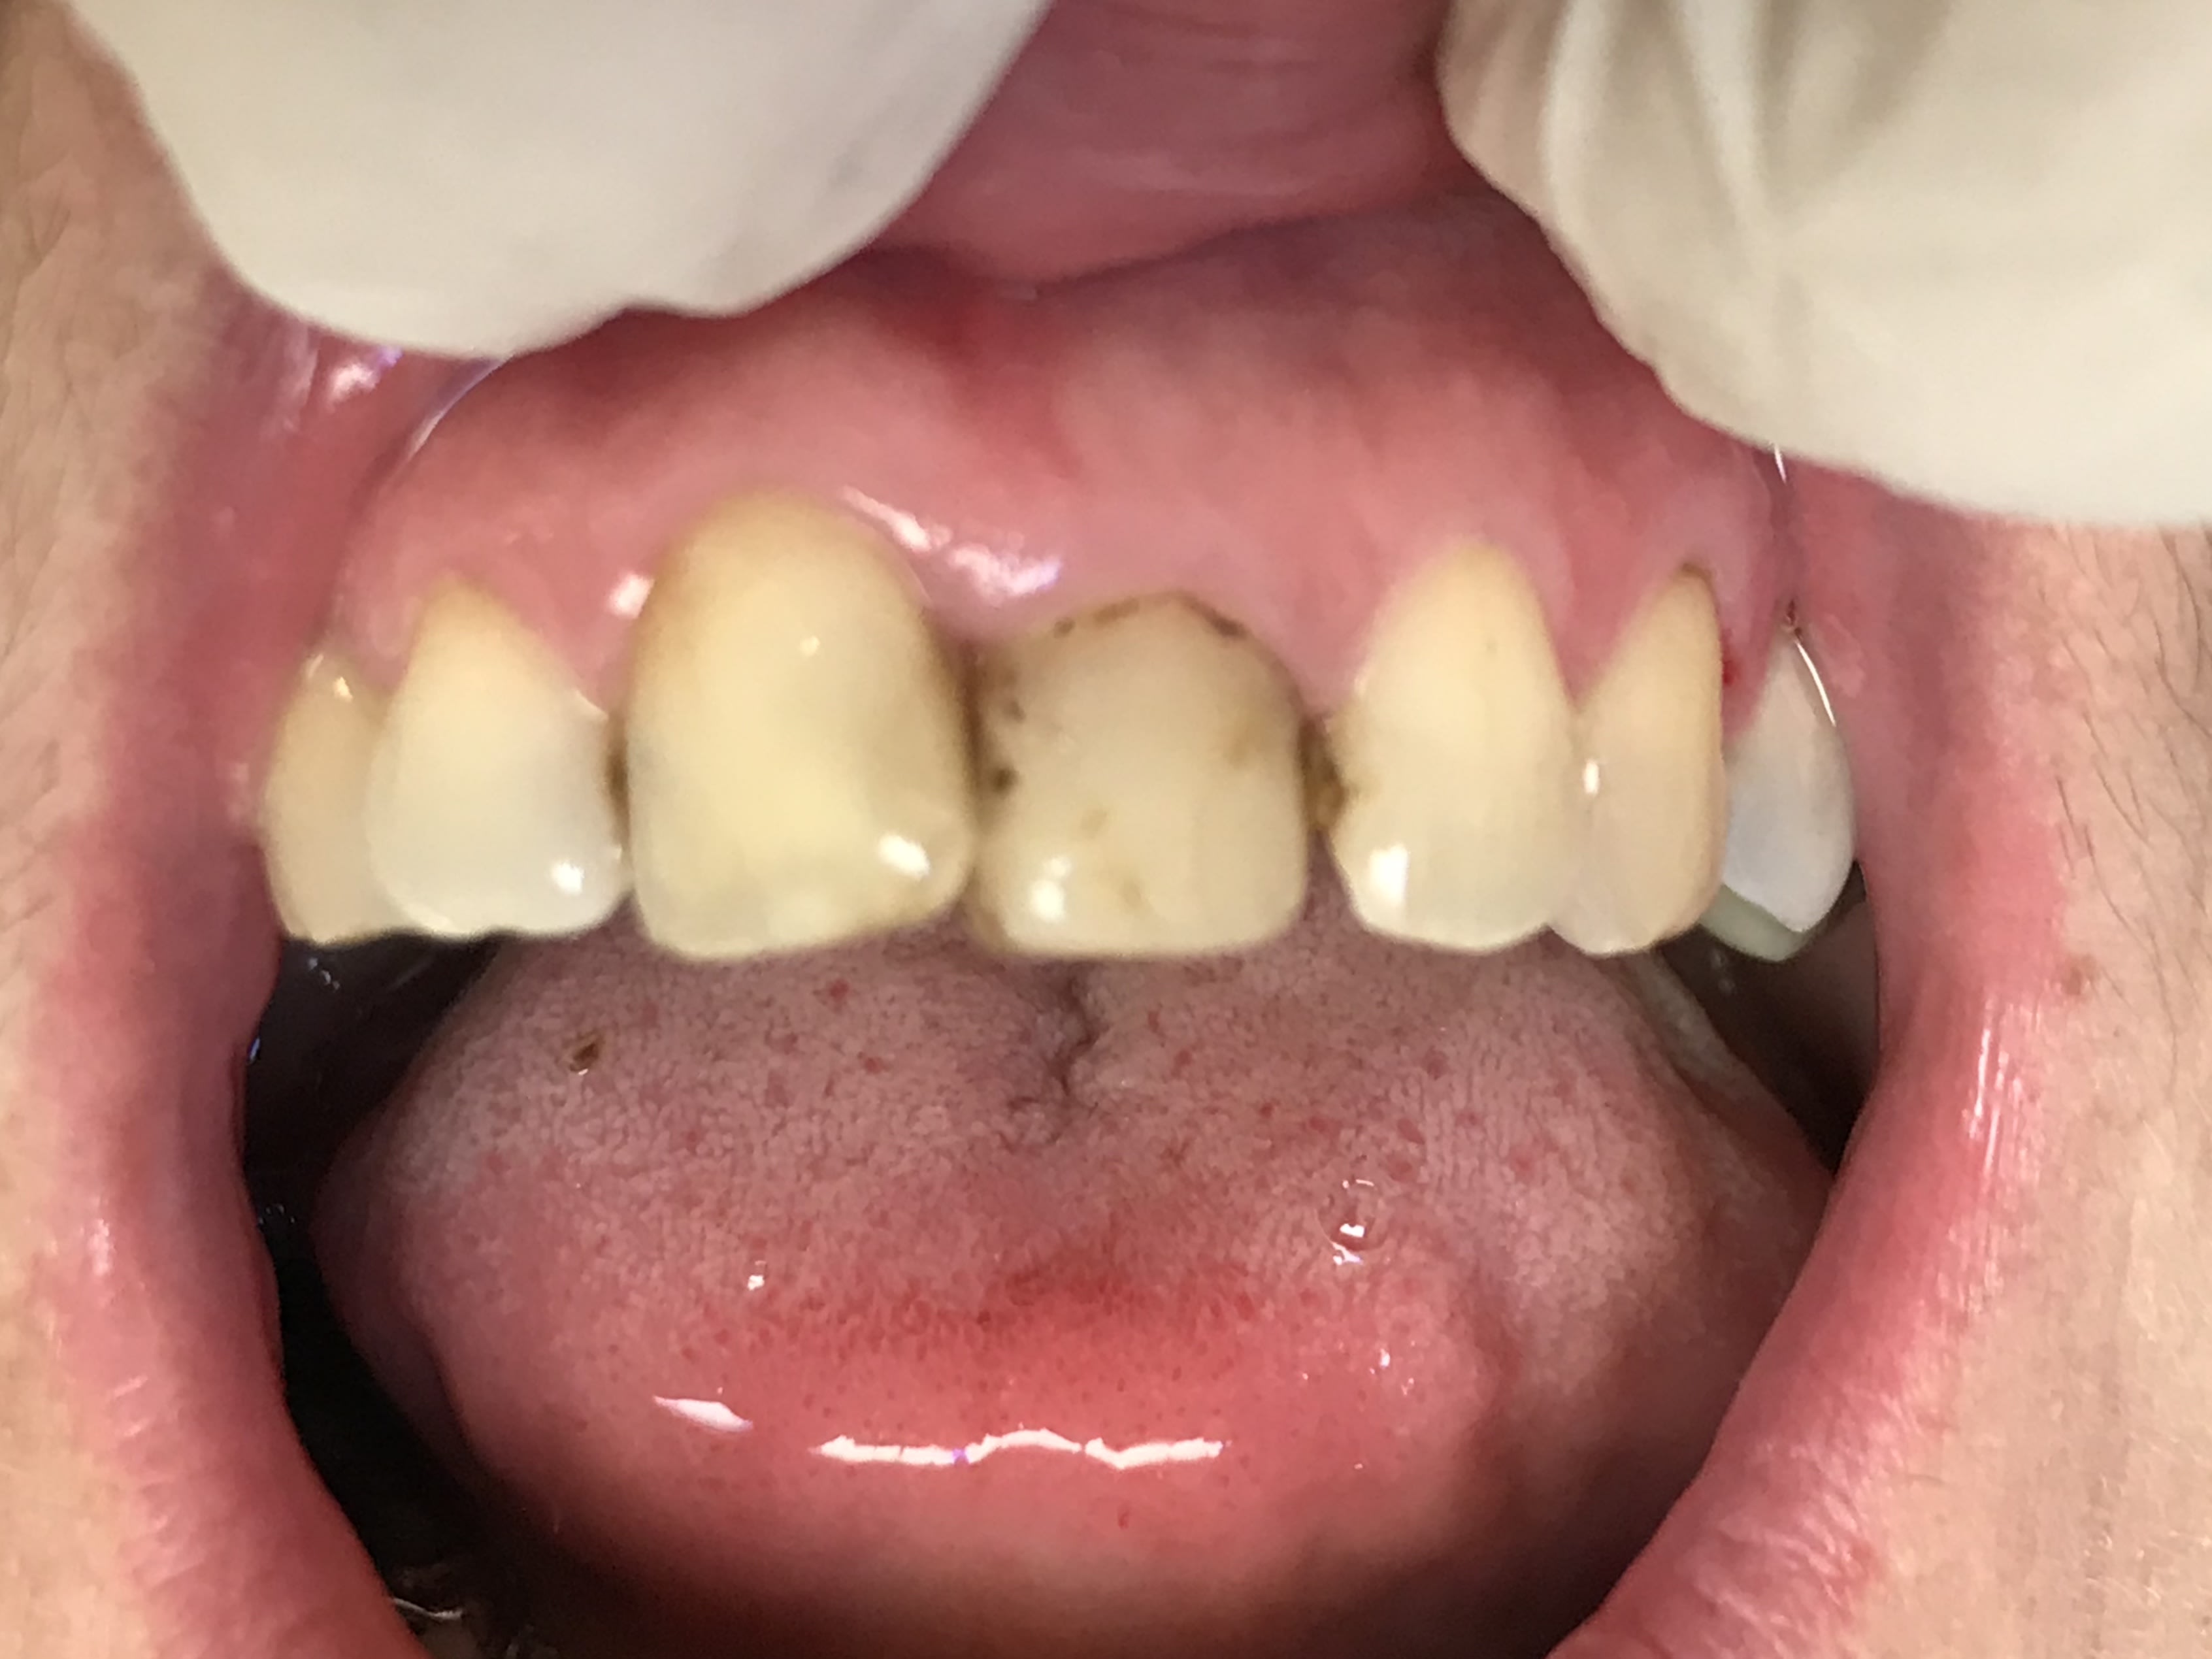

Parce que le composite tient bien dans le temps , une facette en composite avec retour palatin a été faite sur 21. Je récupère la patiente et je note la Durabilité ainsi que l’esthétisme du composite +++. Ça tient bien dans le temps.

Ouais, il a raison Junior, le composite c'est rien que de la merde, ça rend aucun service, ça vieillit super mal...de la daube quoi!

En plus sur le cas avec les diadèmes, y'a pas eu de digue....un travail de gros porc quoi!